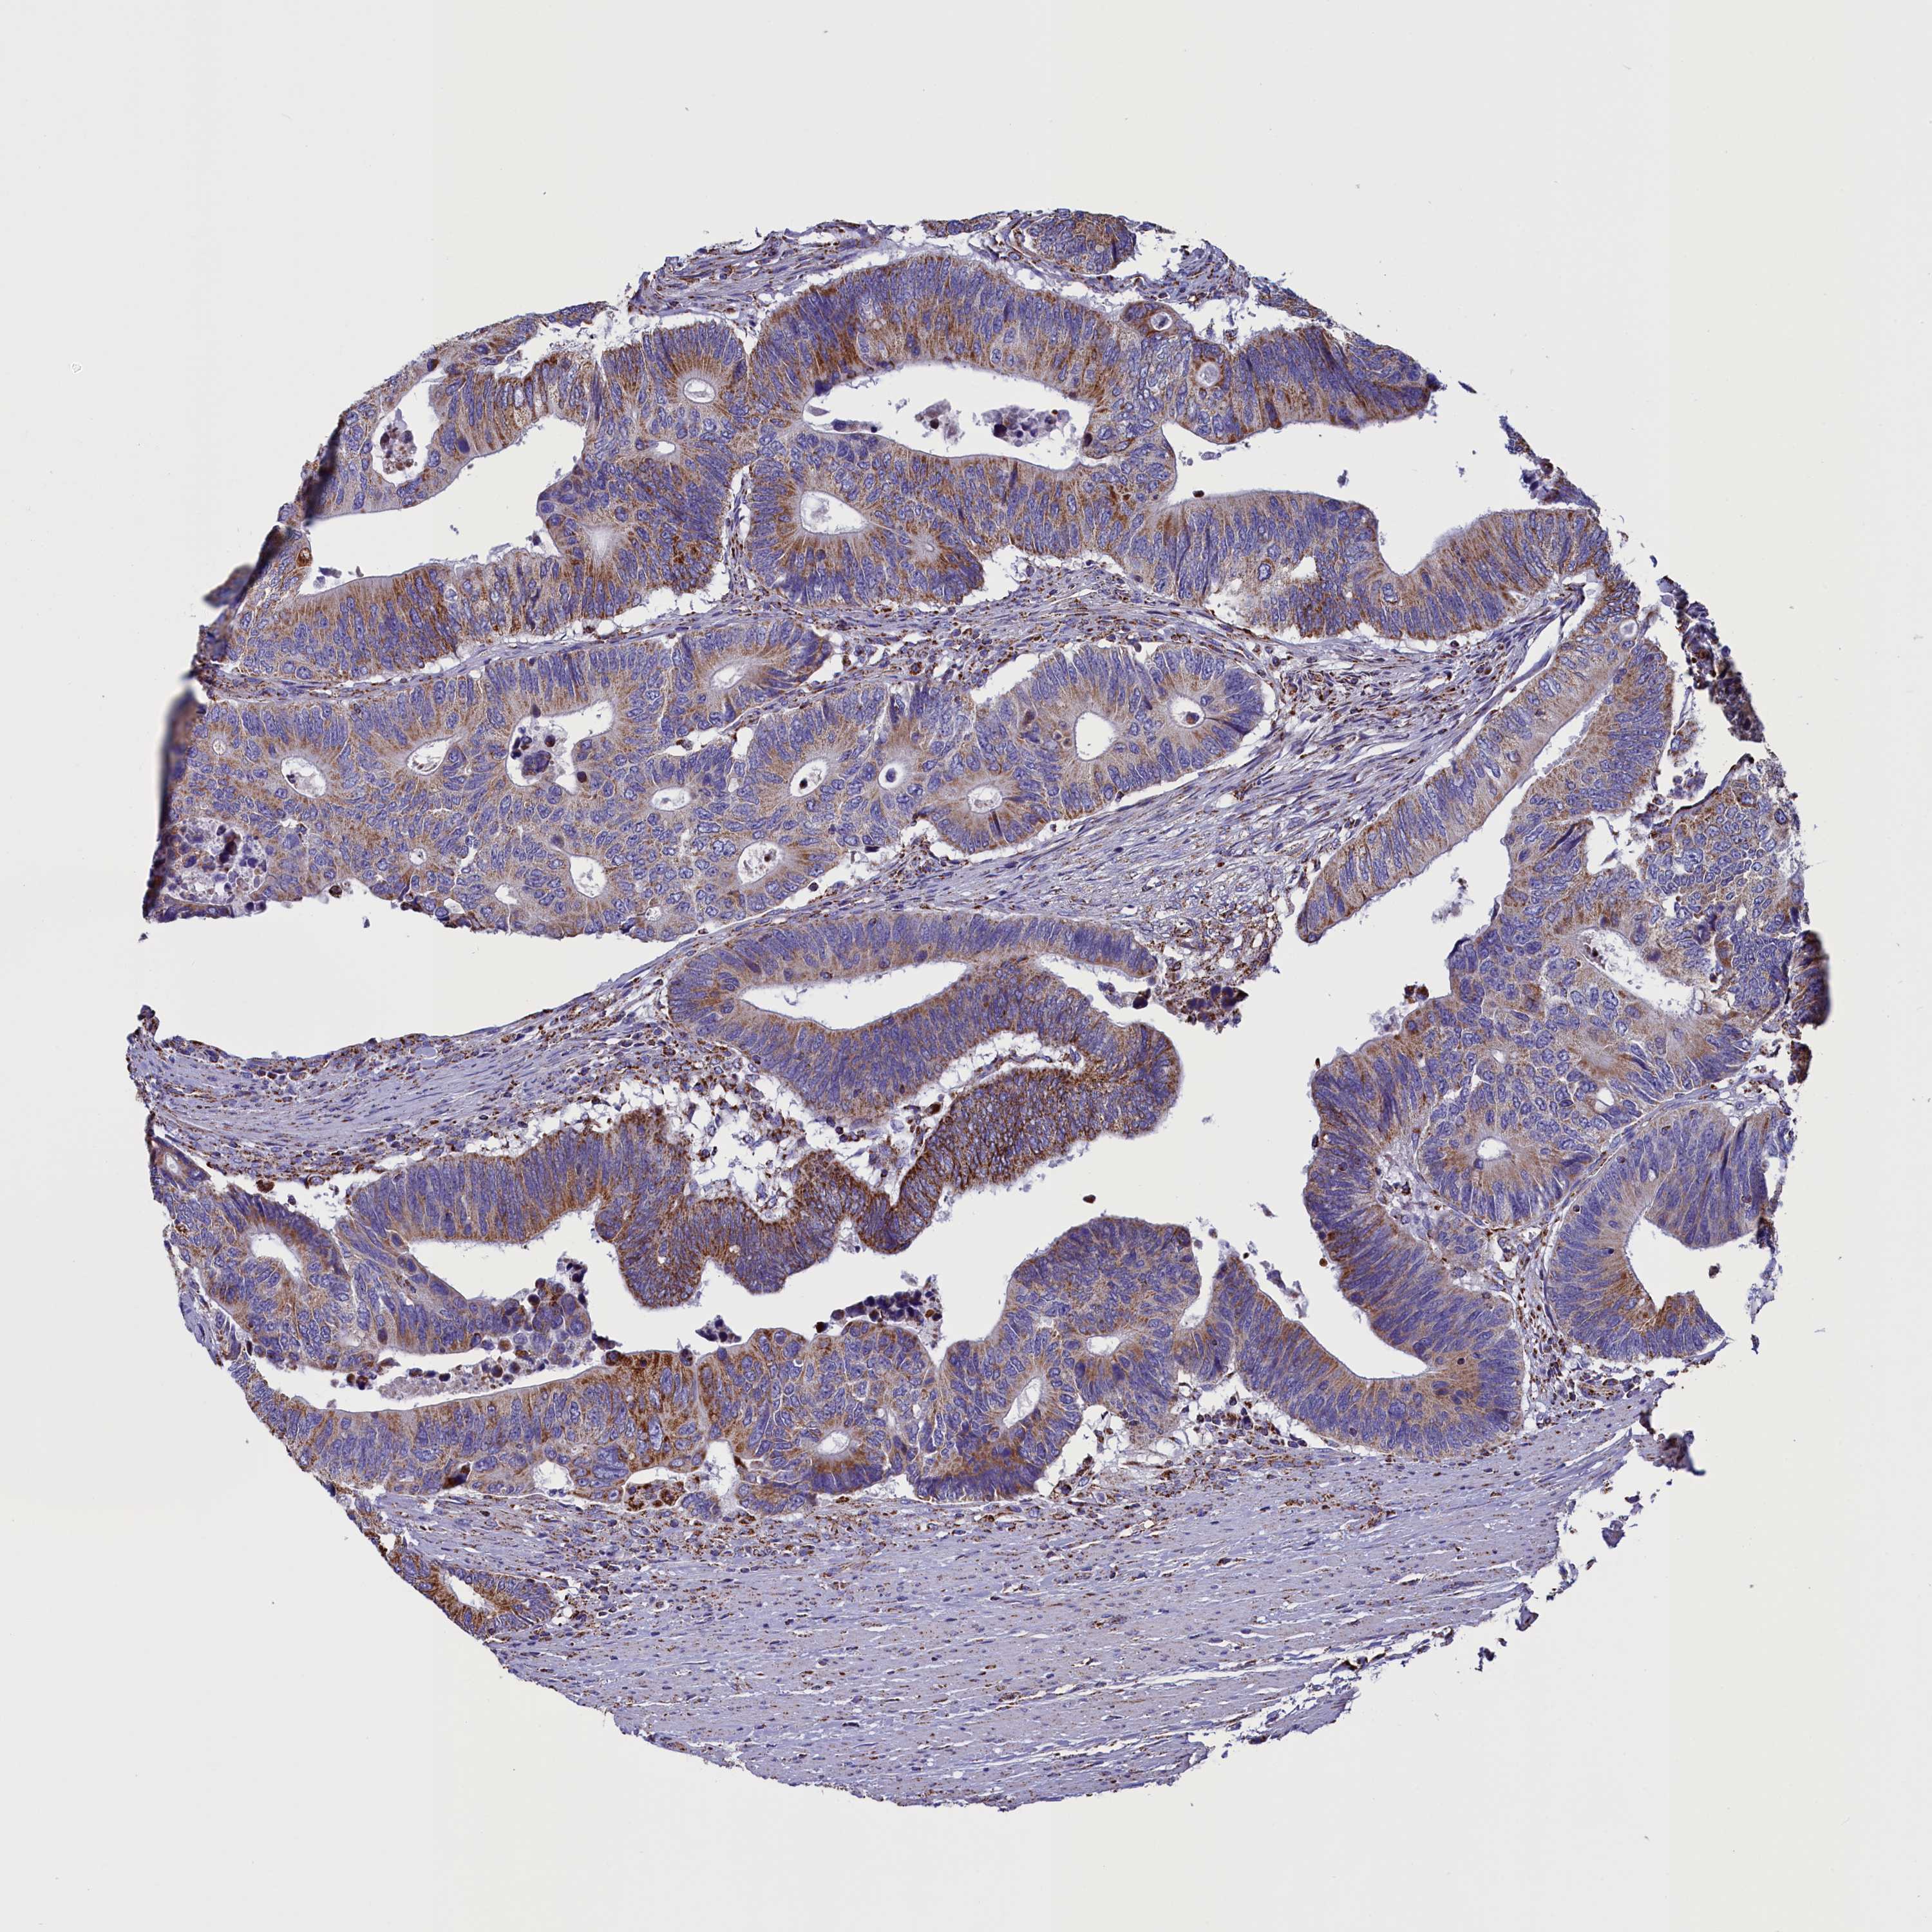

CANCER COLORECTAL CANCER Show tissue menu

Colorectal cancer

Human cancer

Colon adenocarcinoma

Rectum adenocarcinoma